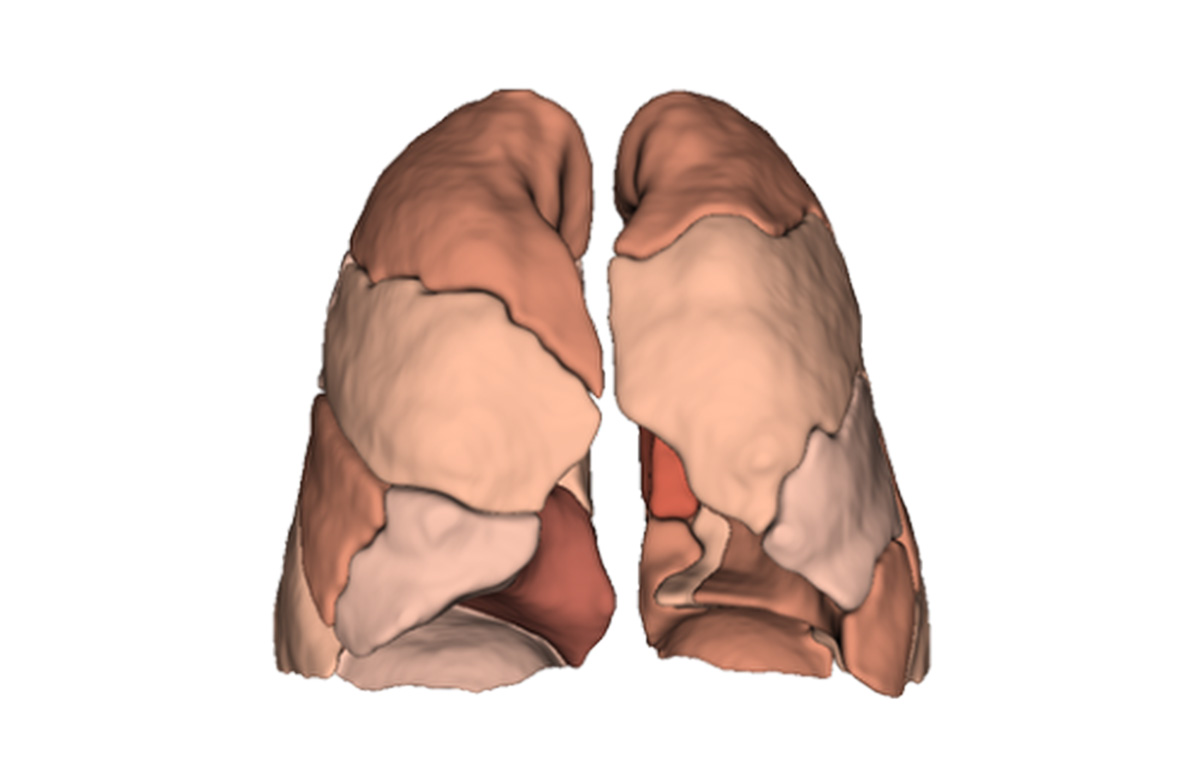

Built on advanced capabilities in lung segmentation and quantification, our AI technology interprets thoracic CT data with anatomical precision - capturing airway trees, parenchymal patterns, and vascular structures, even in severely diseased lungs.

- Segmentation of anatomical structures up to sub-segmental level

- Quantitative analysis of complex lung patterns and diseased regions